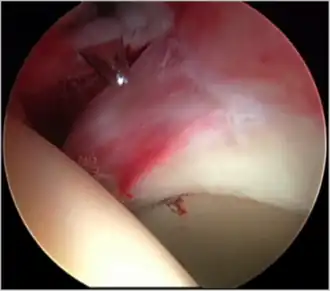

- Figure 5. Portal placement under direct vision. The instrument is entering the joint through the hip capsule, between the femoral head (on the left) and acetabular labrum (on the right)

The next step is to insert a fine needle under x-ray guidance into the hip joint. This breaks the 'suction seal' of the joint and allows further distraction if necessary (see fig 4). The surgeon wishes to see the ball move out the socket by approximately 1 cm, so that access to the hip joint can be achieved with minimal risk of damage to the joint surfaces. Most surgeons will inject fluid into the joint at this stage, again to ensure that there is enough space between the ball and socket for safe instrument access. This needle is then removed. The next step is placement of the 'portals', or the small holes made to pass instruments into the joint. This is achieved by again passing a fresh hollow needle into the joint under x-ray control, usually in a slightly different position. The reason for this is so the surgeon can ensure that the needle, and subsequent cannulae do not penetrate and damage the acetabular labrum or cartilage joint surfaces (see fig. 5). Again, surgeons will have their own preferences as to their preferred placement. Through this hollow needle, a long thin flexible guide wire is passed into the joint, and the needle is removed over it, leaving the guide wire in situ. A small cut in the skin is made around the wire, to allow for larger cannulae to be placed over the wire through the portal. The wire therefore guides the larger cannulae into the joint. The most common external diameters of cannulae used are between 4.5 and 5.5 mm. Once the surgeon is satisfied that the cannula is in the correct position, by a combination of feel and x-ray guidance, the guide wire can be withdrawn. Once the first portal is correctly placed, any further portals may be created once the camera is in position, to ensure that they are placed with minimal risk to the joint surfaces. This process can be repeated to gain as many points of entry to the hip joint as the surgeon requires, normally between two and four. Certain of these entry points will be used for the viewing arthroscope and others for operating instruments.